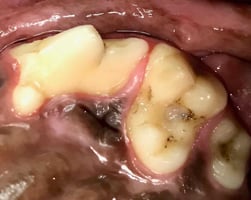

Recognising malocclusion in dogs and cats

“She still eats, plays and shows no signs of any pain” and “the breeder told me that it is normal” a...